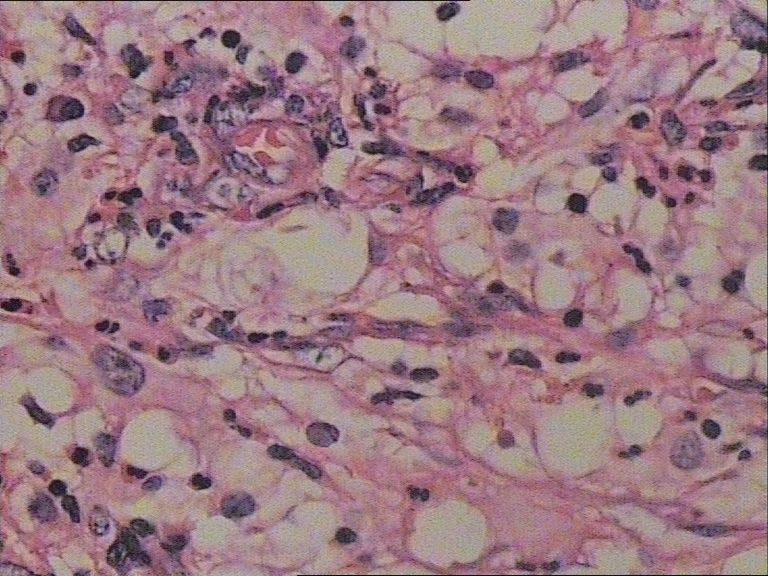

患者    女    47岁    腰部皮下肿块5x4cm,皮肤表面灰褐色,无隆起,无压痛。体格检查无其他异常。

是的,拿来给大家看的主要原因是本病细胞学比组织学特征更明显。

图片很清晰,挺好,就是看不明白,好像就是很多的多核巨细胞和炎细胞?似乎还有真菌菌丝似的东西?似乎是个肉芽肿病变,还得做活检手术吧?

单核及多核组织细胞是本病不特异但恒定的特点,可惜高倍镜图片看不清核结构,显微镜下很清楚。

纤维黄色瘤

最后诊断为Rosai-Dorfman病。